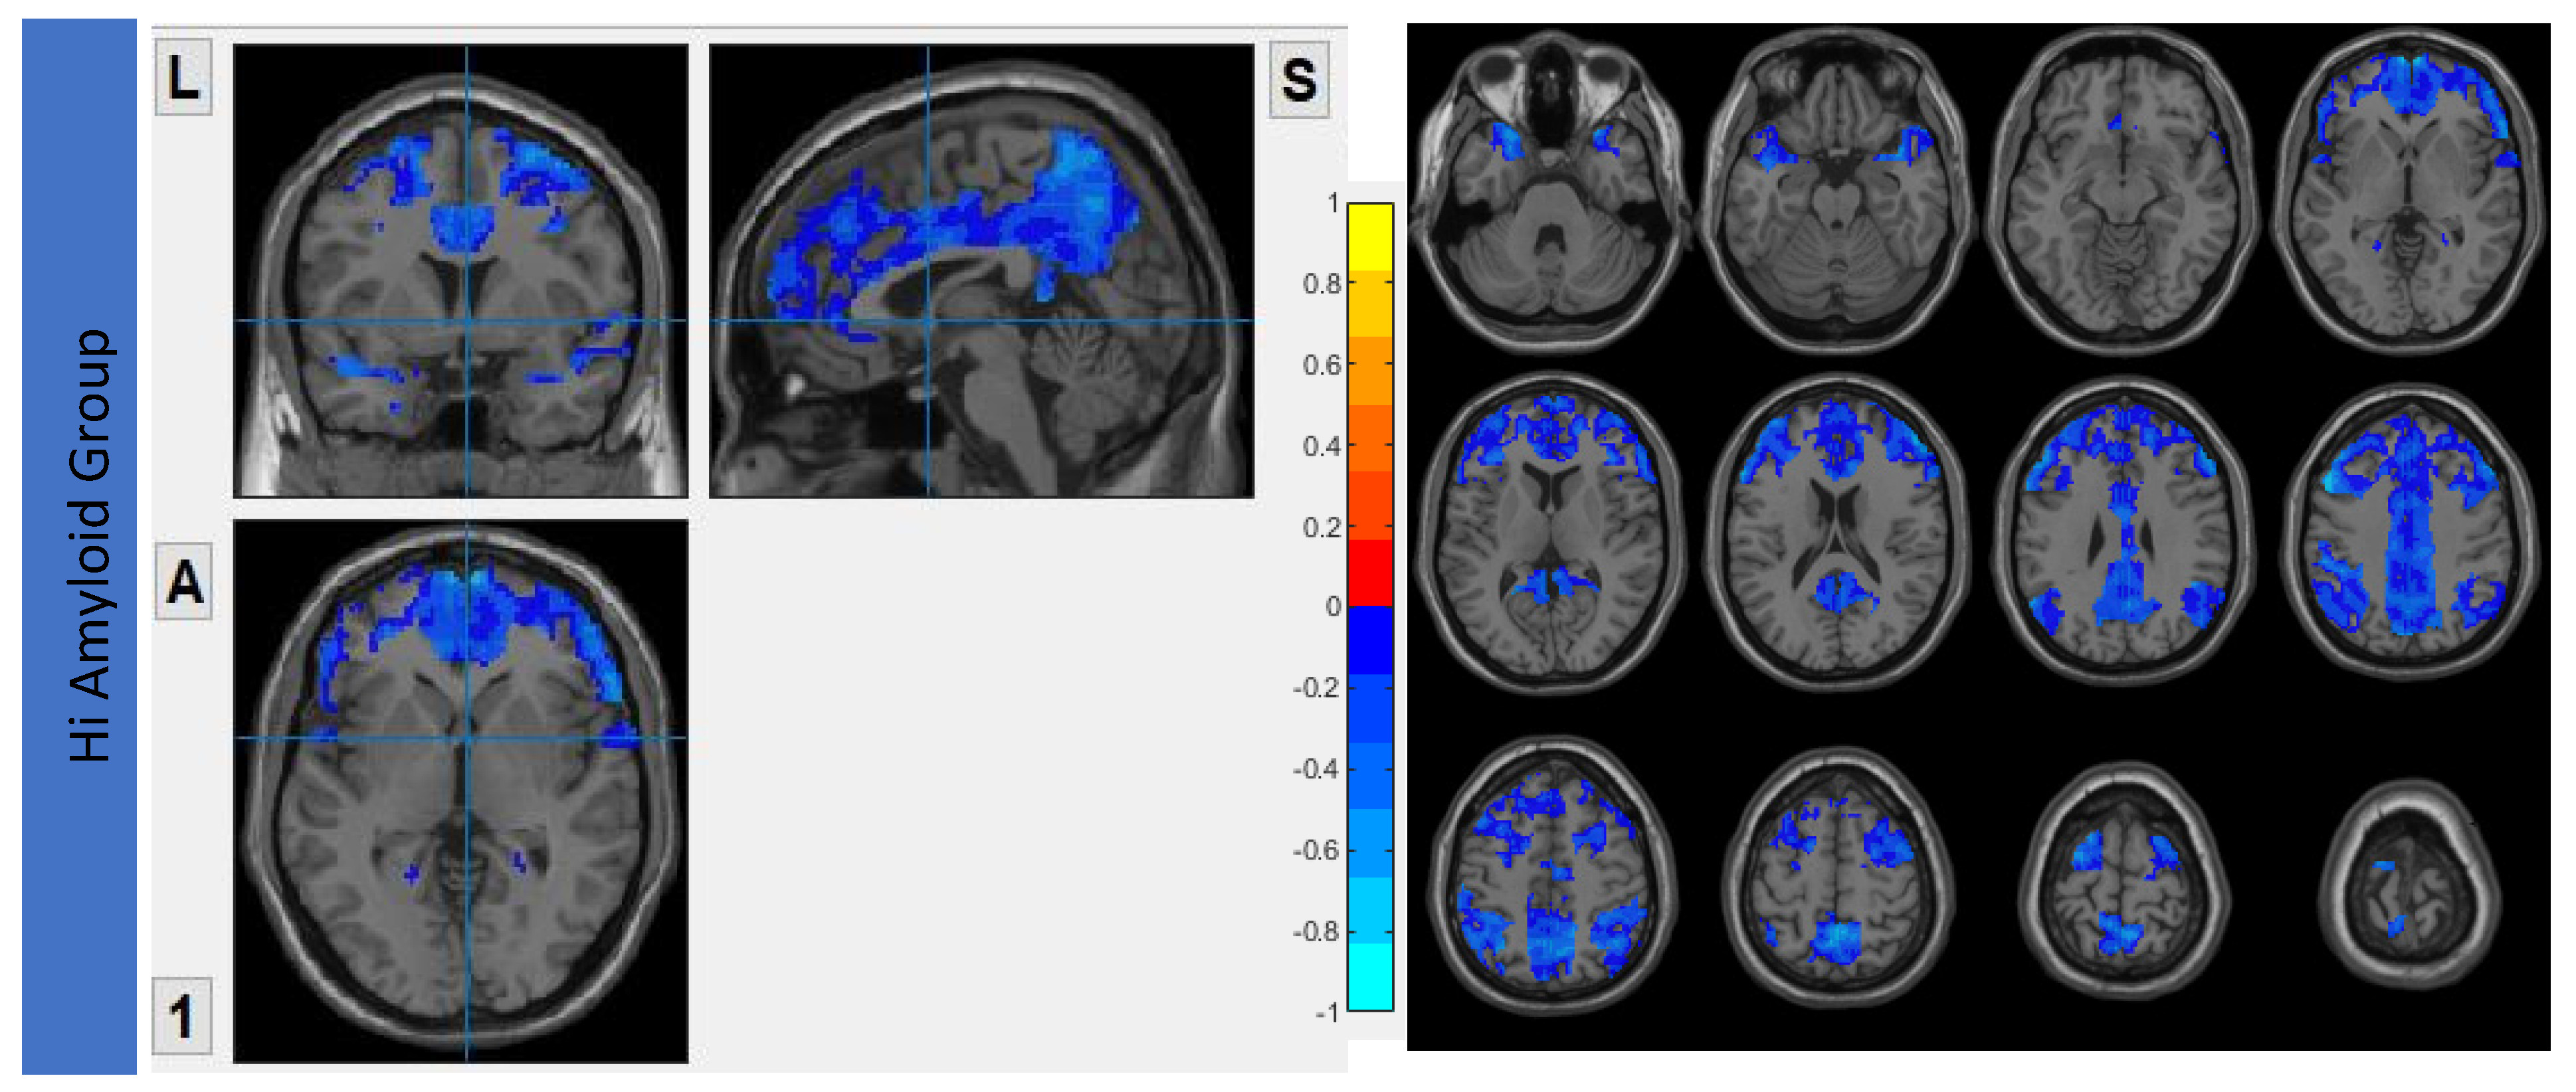

6.3. Interhemispheric Functional Connectivity (VMHC) Maps

7.1. Within DMN